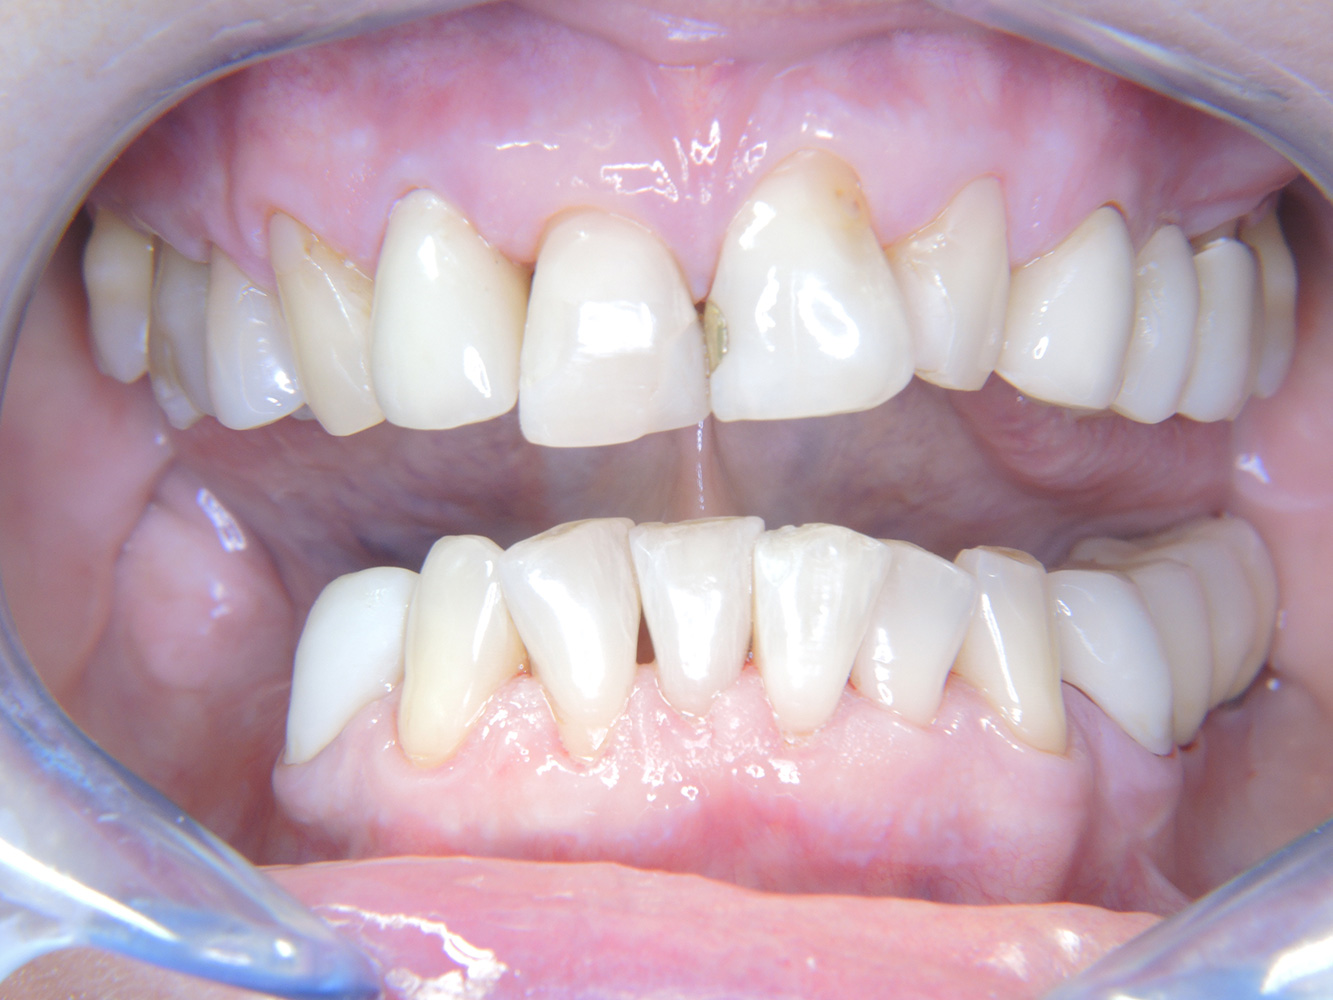

Paciente sana con enfermedad periodontal previa*

La paciente de 68 años no tiene enfermedades previas relevantes de la salud general ni toma medicación; sus hábitos alimentarios tampoco suponen un riesgo especial. La paciente tiene dos implantes (tercer cuadrante, desde hace cinco años) y una enfermedad previa periodontal (periodontitis en etapa IV, grado B) con pérdida dental. Actualmente las condiciones periodontales son estables, pero la periodontitis aumenta de manera determinante las complicaciones biológicas cuando se realizan implantes y puede ocasionar la pérdida de un implante (21). Para la sesión de profilaxis se hacen cuatro recomendaciones.

Dado que la paciente no tiene factores de riesgo especiales con efectos específicos para los dientes, las necesidades determinadas a partir de la salud oral son determinantes. Se recomienda un estado periodontal detallado una vez al año. De esta forma, es posible responder a la posible progresión de la enfermedad periodontal previa o al desarrollo de periimplantitis a tiempo.

Debido a la situación del implante con la enfermedad periodontal previa, la paciente tiene riesgo de desarrollar periimplantitis; se recomienda un intervalo de recuperación de tres a cuatro meses.